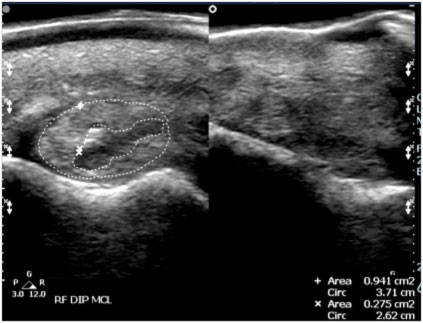

Example 1: 11-year-old quarter horse

History: Moderate tear of the medial collateral ligament of the right front coffin joint.

Left image: Sonogram of medial collateral ligament of right front coffin joint, showing enlarged cross-sectional area and a fresh-appearing core lesion.

Ultrasound Impressions: Image on the right was taken 3 months after image on the left and according to the veterinarian it shows reduced effusion and reduced synovitis in comparison with the previous examination. He stated that the lateral collateral ligament was normal and there has been a decrease in inflammation in the coffin joint and good granulation in the core lesion of the medial collateral ligament. Horse was treated twice daily on the Vitafloor.